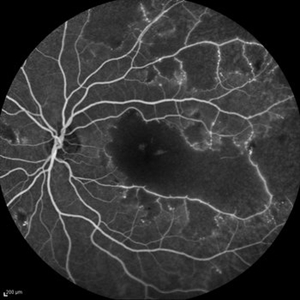

Behcet's Disease Behcet's DiseaseMar 13 2013 by Hamid Ahmadieh, MD Early phase FA of the right eye of a 23-year-old man with retinal vasculitis and branch retinal vein occlusion (BRVO) due to Behcet's disease . Photographer: Solmaz Shahmohammad, Negah Eye Center, Tehran Imaging device: Heidelberg Spectralis Condition/keywords: branch retinal vein occlusion (BRVO), retinal vasculitis